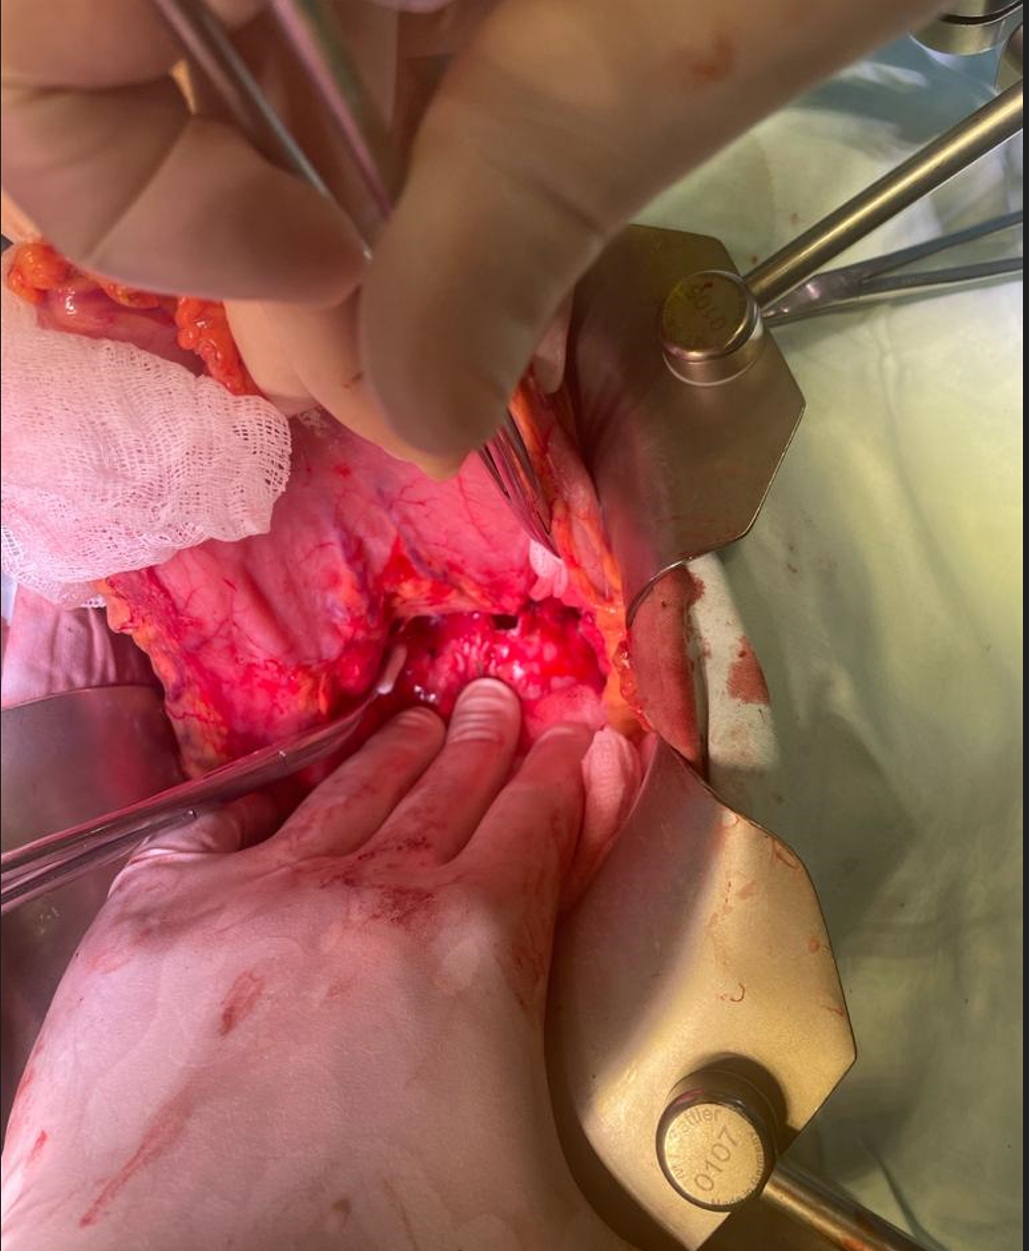

08.07.2021 г. под эндотрахеальным наркозом в положении пациента на спине выполнена верхне-срединная лапаротомия с обходом пупочного кольца слева. В брюшной полости выпота нет. Произведена ревизия брюшной полости: печень, желчный пузырь, желудок, селезенка, тонкий и толстый кишечник, органы малого таза без патологии, париетальная и висцеральная брюшина не изменена. Пересечена круглая и серповидная связки печени, мобилизована ее левая доля с визуализацией аортального и пищеводного отверстий диафрагмы. При вскрытии сальниковой сумки отмечен выраженный спаечный процесс с вовлечением задней стенки желудка, передней поверхности ПЖ, структур чревного ствола. При дальнейшей мобилизации желудка, на передней поверхности тела ПЖ вскрыта псевдокиста до 2,5-3 см и свищевой ход, диаметром 5-6 мм, заполненные панкреатическим соком. Свищевой ход имеет хорошо выраженные плотные стенки, уходит по забрющинному пространству вверх, в средостение (рис. 2,3).

Рис. 2. Интраоперационное фото. Свищевой дефект передней поверхности тела поджелудочной железы.

Fig. 2. Intraoperative photo. Fistulous defect of the anterior surface of the body of the pancreas.

Рис. 3. Интраоперационное фото. Псевдокиста передней поверхности тела поджелудочной железы, устье свищевого хода.

Fig. 3. Intraoperative photo. Pseudocyst of the anterior surface of the body of the pancreas of the body, the mouth of the fistula.